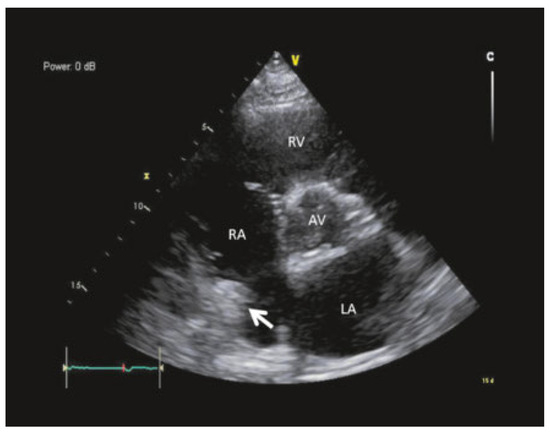

Case report